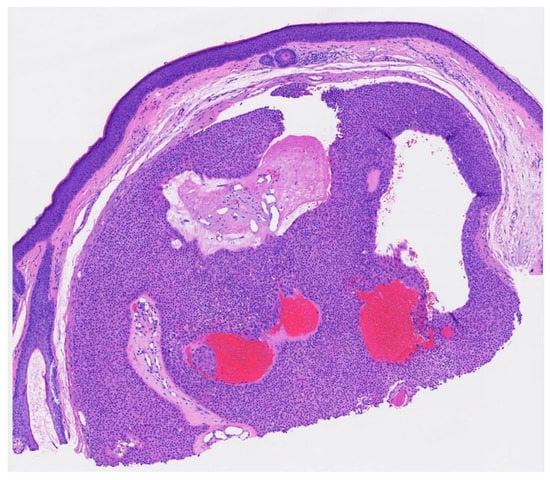

Figure 3. Well circumscribed, dermal-based, solid and cystic tumor with no connection to the overlying epidermis (H & E, 2×).

Poroma variants are differentiated based on the predominant cell type present and the degree of epidermal/dermal involvement [2]. However, multiple variants can exist within the same lesion. DDTs are primarily confined to the superficial dermis and are composed of small solid and cystic nodular aggregates of poroid, cuticular, and clear cells (Figure 3, Figure 4 and Figure 5) [2]. Eccrine poromas are also composed of all three cell types, but are primarily located in the epidermis and superficial dermis. Hidroacanthoma simplex is mainly composed of poroid cells, less cuticular cells, and no clear cells [2]. It is confined to the epidermis. Poroid hidradenoma contains a mixture of all three cell types and is also confined to the dermis [2]. In contrast to DDT, poroid hidradenomas have large aggregates of solid and cystic components and extend deeper into the reticular dermis and even subcutis [2].

The histopathologic diagnosis of DDT is rare due, in part, to the fact that some regard DDTs as poromas with a limited epidermal connection that has not been identified on the histologic sections examined or as hidradenomas that are smaller and more superficial [30]. As an example, Figure 3 may be regarded by some as representing a hidradenoma. This controversy in the histopathologic classification of poroid neoplasms without clear-cut evidence for the clinical significance of distinguishing these lesions from each other has given rise to the thinking that the poroma classification scheme may just be a matter of semantics [19]. This has led to some pathologists diagnosing these lesions under the overarching term as “acrospiroma” only without further classification.